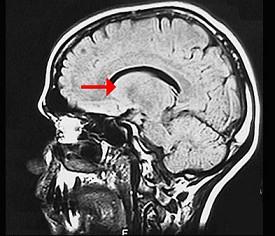

如图箭头所示为大脑哪个部位 ( )A、松果体B、中脑导水管C、豆状核D、尾状核E、丘脑

问题 如图箭头所示为大脑哪个部位 ( )

选项 A、松果体 B、中脑导水管 C、豆状核 D、尾状核 E、丘脑

答案 D